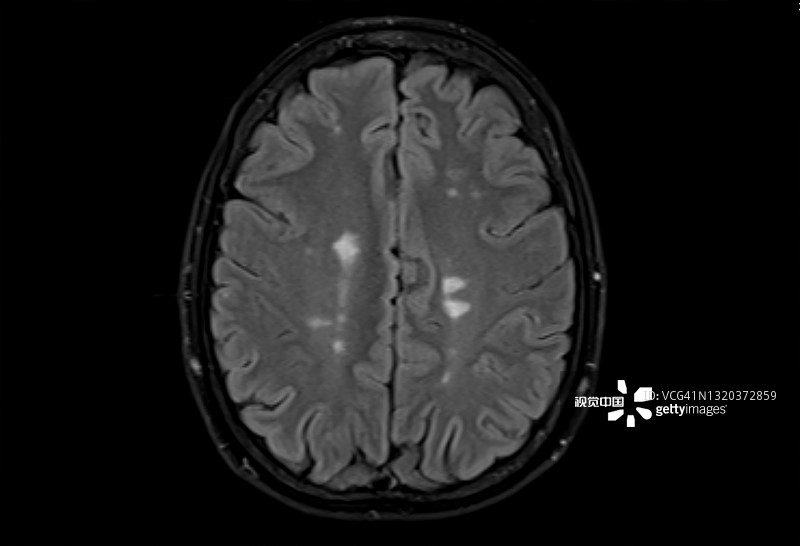

多發(fā)性硬化癥 (MS):MS是一種中樞神經(jīng)系統(tǒng) (CNS) 的慢性自身免疫和炎癥性疾病。MS與免疫系統(tǒng)介導的自身反應(yīng)性T細胞和B細胞對神經(jīng)元髓鞘的攻擊有關(guān),導致脫髓鞘并最終導致神經(jīng)元丟失。由于中樞神經(jīng)系統(tǒng)中神經(jīng)變性和斑塊的形成,MS患者會根據(jù)斑塊的位置經(jīng)歷特定的神經(jīng)功能障礙。例如,視神經(jīng)中的斑塊會導致視力喪失。